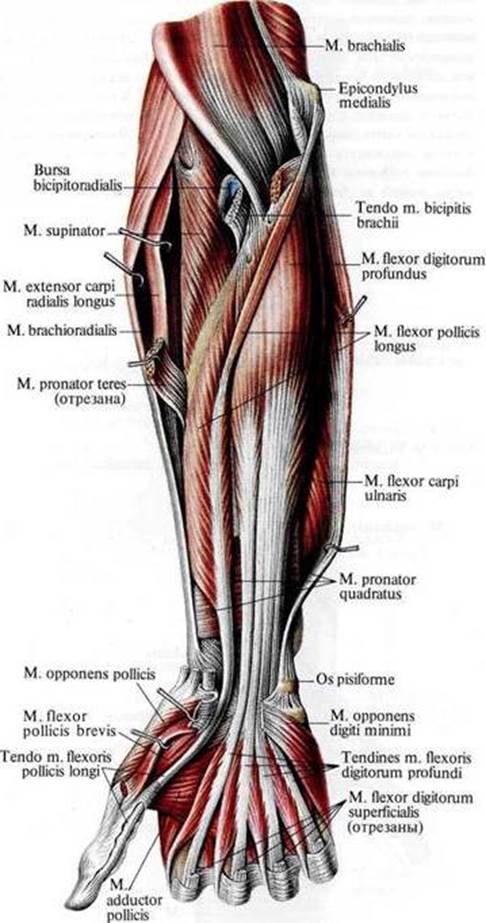

Анатомия и функции мышцы brachioradialis